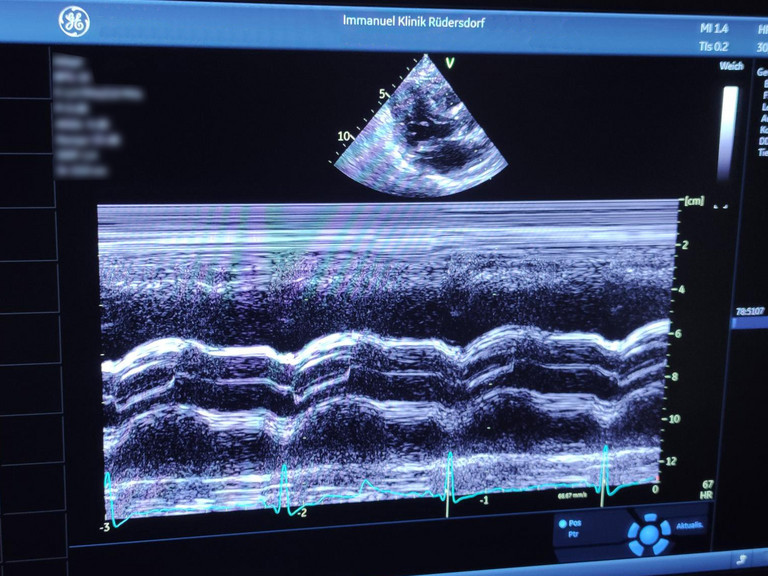

Die Abteilung sichert die internistische stationäre Versorgung aller Altersstufen der Erwachsenenbevölkerung der Region. Sie setzt dabei Behandlungsschwerpunkte in der Gastroenterologie, Kardiologie, Diabetologie und Hämatologie bzw. Onkologie. Medizinisches Know-how, modernste Technik und fürsorgliche Begleitung sind Grundlagen für einen Behandlungsverlauf.